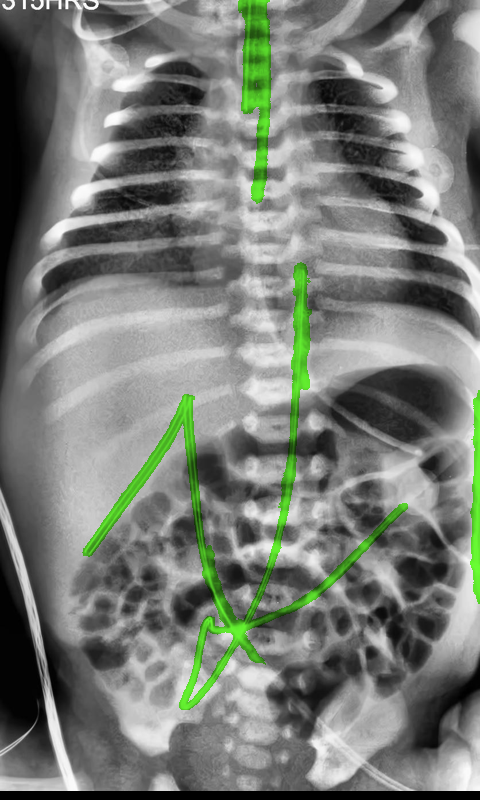

Automated catheter detection is a challenging task. Although most catheters have a radiopaque strip to facilitate detection, the strip may become less apparent depending on the projection angle. Catheters maybe confused by other similar linear structures like ECG leads and anatomy including ribs. Additionally, portions of catheters can be occluded by anatomical structures given that radiographs are a 2D projection of a 3D structure. For example, when a NGT is placed within the oesophagus, the catheter itself becomes less apparent due to the high density of the adjacent vertebrae. Finally, the number and type of catheters that could possibly appear in pediatric X-rays are unknown a priori. The catheters may be intertwined with each other thus making simple line tracing methods fail. Figure 1 gives three sample pediatric X-ray images with some common catheters highlighted in different colors.

To alleviate this annotation problem in catheter detection, we proposed to use X-ray images with simulated catheters by exploiting the fact that catheters are essentially tubular objects with various cross sectional profiles. To be more specific, a synthetic 2D projection of a catheter is generated by first simulating a horizontal catheter profile and then using it as a brush tip to draw along a B-spline path. This generated catheter is then composited with an X-ray image serving as the training data. Another contribution of this work is a segmentation network that can inherently take into account multi-scale information. This network adopts a UNet-style form and contains a recurrent module that can process inputs with increasing scales111Our code is available at https://github.com/xinario/catheter_detection.git.. We have empirically shown that by iterating through the scale space of the input image, higher recall is achieved as compared to using a single scale. Details about the methods are discussed in Section 3. Three sample detection results are shown in Figure 1.

The test dataset is collected locally and only contains frontal chest-abdominal X-rays from patients < 4 weeks old. This is the most common radiograph obtained to confirm placement of catheters such as UACs and UVCs in neonates. Currently, the test set has 35 fully labeled images with different catheter types with sample images previously shown in Figure 1. All the annotated catheters (lines excluding ECG leads) are treated as the same class in the detection.